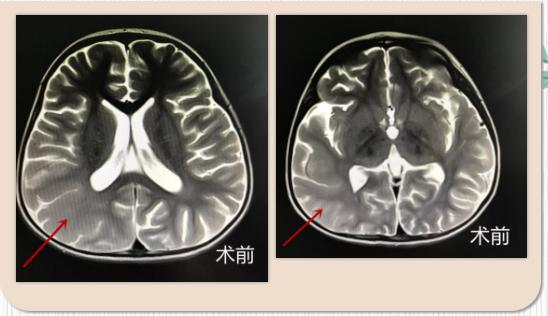

周焕斌教授细细询问病史,查看检查结果后,告知小蕊家人,考虑是:巨脑回畸形、灰质异位导致难治性癫痫。

什么是巨脑回畸形、灰质异位?是先天性的吗?手术治疗后能痊愈吗?癫痫会不会再发作吗?会影响孩子的发育吗?.......孩子的妈妈一连串问出了好多的疑惑和担忧。周焕斌教授耐心细致的一一回答了家属的问题。他表示:巨脑回畸形、灰质异位属于小儿先天性脑发育缺陷,经常伴有癫痫。术后去除病症可痊愈,不影响孩子的发育。

通过与北京首都儿研所团队进行多学科讨论后决定行“右侧颞叶切除,颞顶叶离断术”。手术顺利结束后,目前小蕊已转回普通病房,一天数十次的发作神奇般的消失了。